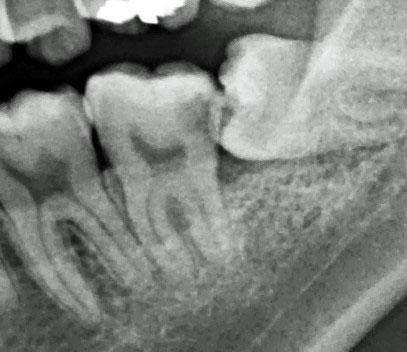

根管治療

虫歯が歯の奥深くまで進むと、歯の根っこの治療が必要になります。この段階まで病気が進行するとかなり歯のダメージは大きくなります。虫歯段階での治療に比べて治療しても歯の強度が劣り、歯の寿命は残念ながら統計上5~10年短くなります。ただし放置してただ歯を失っていくより治療をお受けになることをお勧めします。治療することで歯の噛むことなどの機能回復や審美的回復をして歯の延命が可能になります。稀に、「痛かった歯が、急に痛くなくなった」「虫歯が自然に治った」と勘違いされる方がいらっしゃいます。残念ながら、虫歯は自然に治癒することはありません。神経が死んでしまうと、痛みがいったん止むのです。市販の痛み止めで歯科医院の受診を先延ばしにせず、早めに治療を開始しましょう。